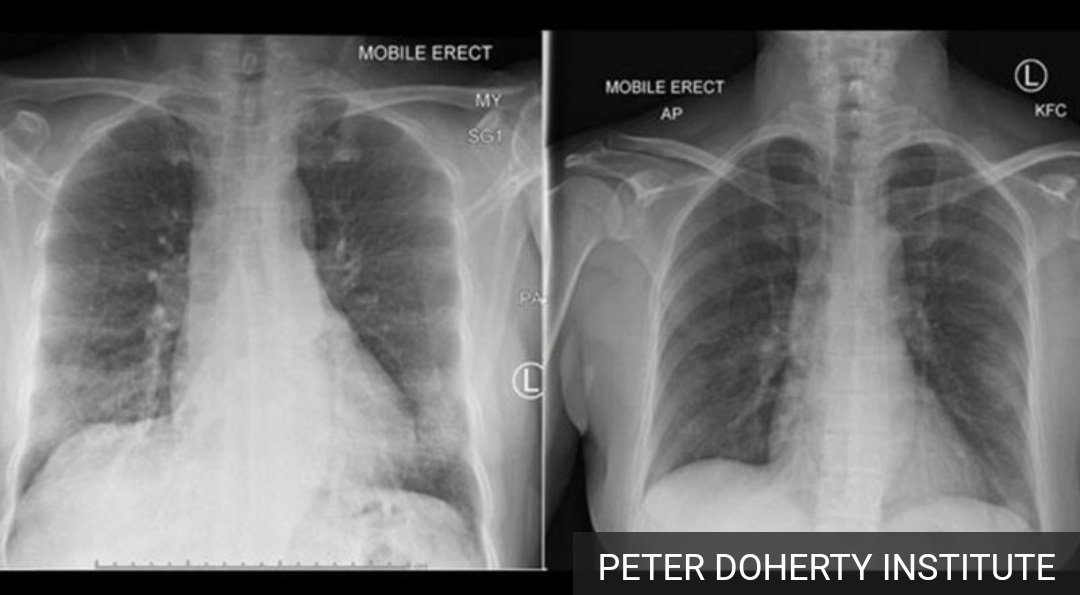

🔸مع كثره عدد الحالات اليوميه أكتسب بعض الأطباء خبرة بإمكانه تشخيص الحاله عن طريق أشعه الصدر مع تحليل الدم وهذه دلاله ع أن الشخص مصاب.